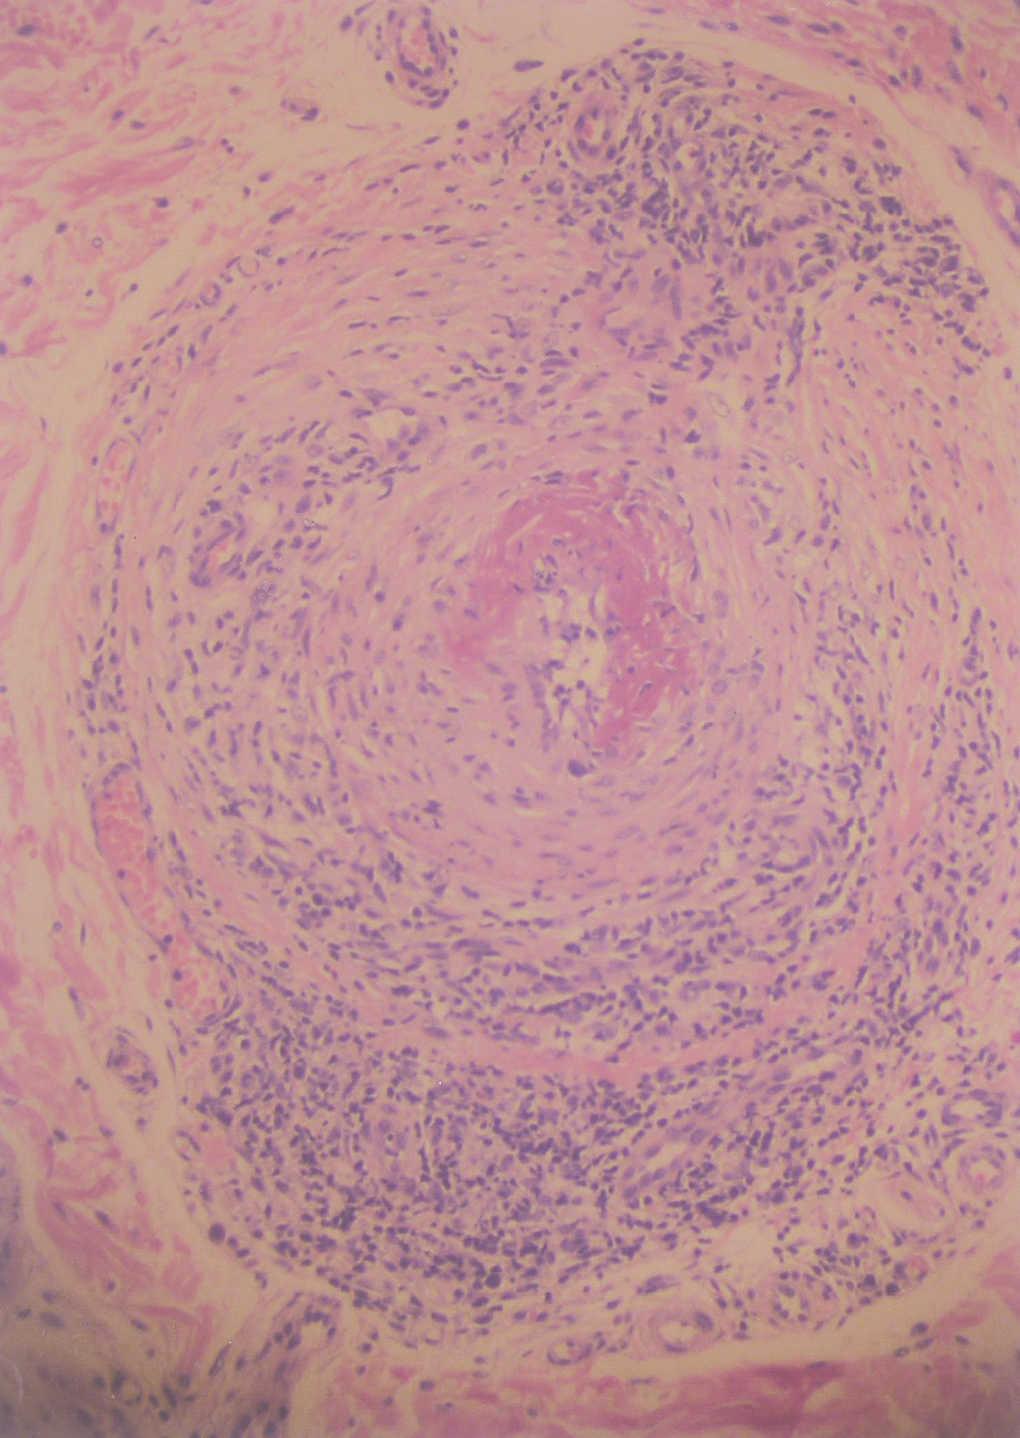

Fig. 3.--Arteritis de un vaso de mediano tamaño localizado en dermis reticular profunda. (Hematoxilina-eosina, x20.)

En la biopsia cutánea se apreciaba una arteria de mediano calibre en la porción inferior de la dermis reticular, con un infiltrado predominantemente linfocitario dispuesto entre y alrededor de las capas de la arteria. La arteria presentaba signos de necrosis fibrinoide (figs. 3 y 4).